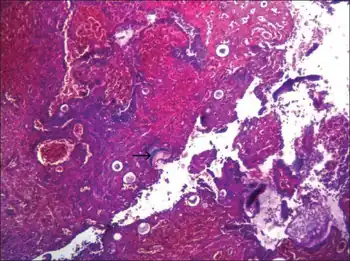

Infection

This organism infects the mucosa of the nasal cavity, producing a mass-like lesion. This mass appears to be polypoidal in nature with a granular surface speckled with whitish spores. The rhinosporidial mass has been classically described as a strawberry-like mulberry mass. This mass may extend from the nasal cavity into the nasopharynx and present itself in the oral cavity. These lesions commonly cause bleeding from the nasal cavity.

R. seeberi can also affect the lacrimal gland and also rarely the skin and genitalia.